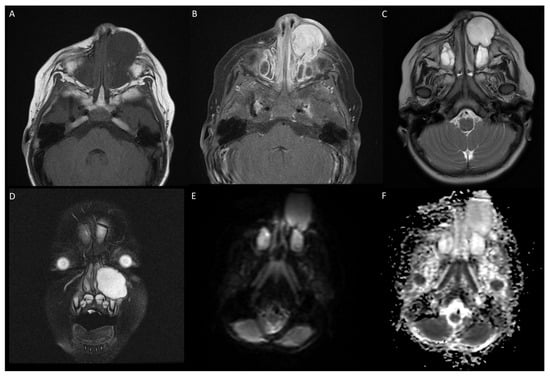

3.1. Case 1